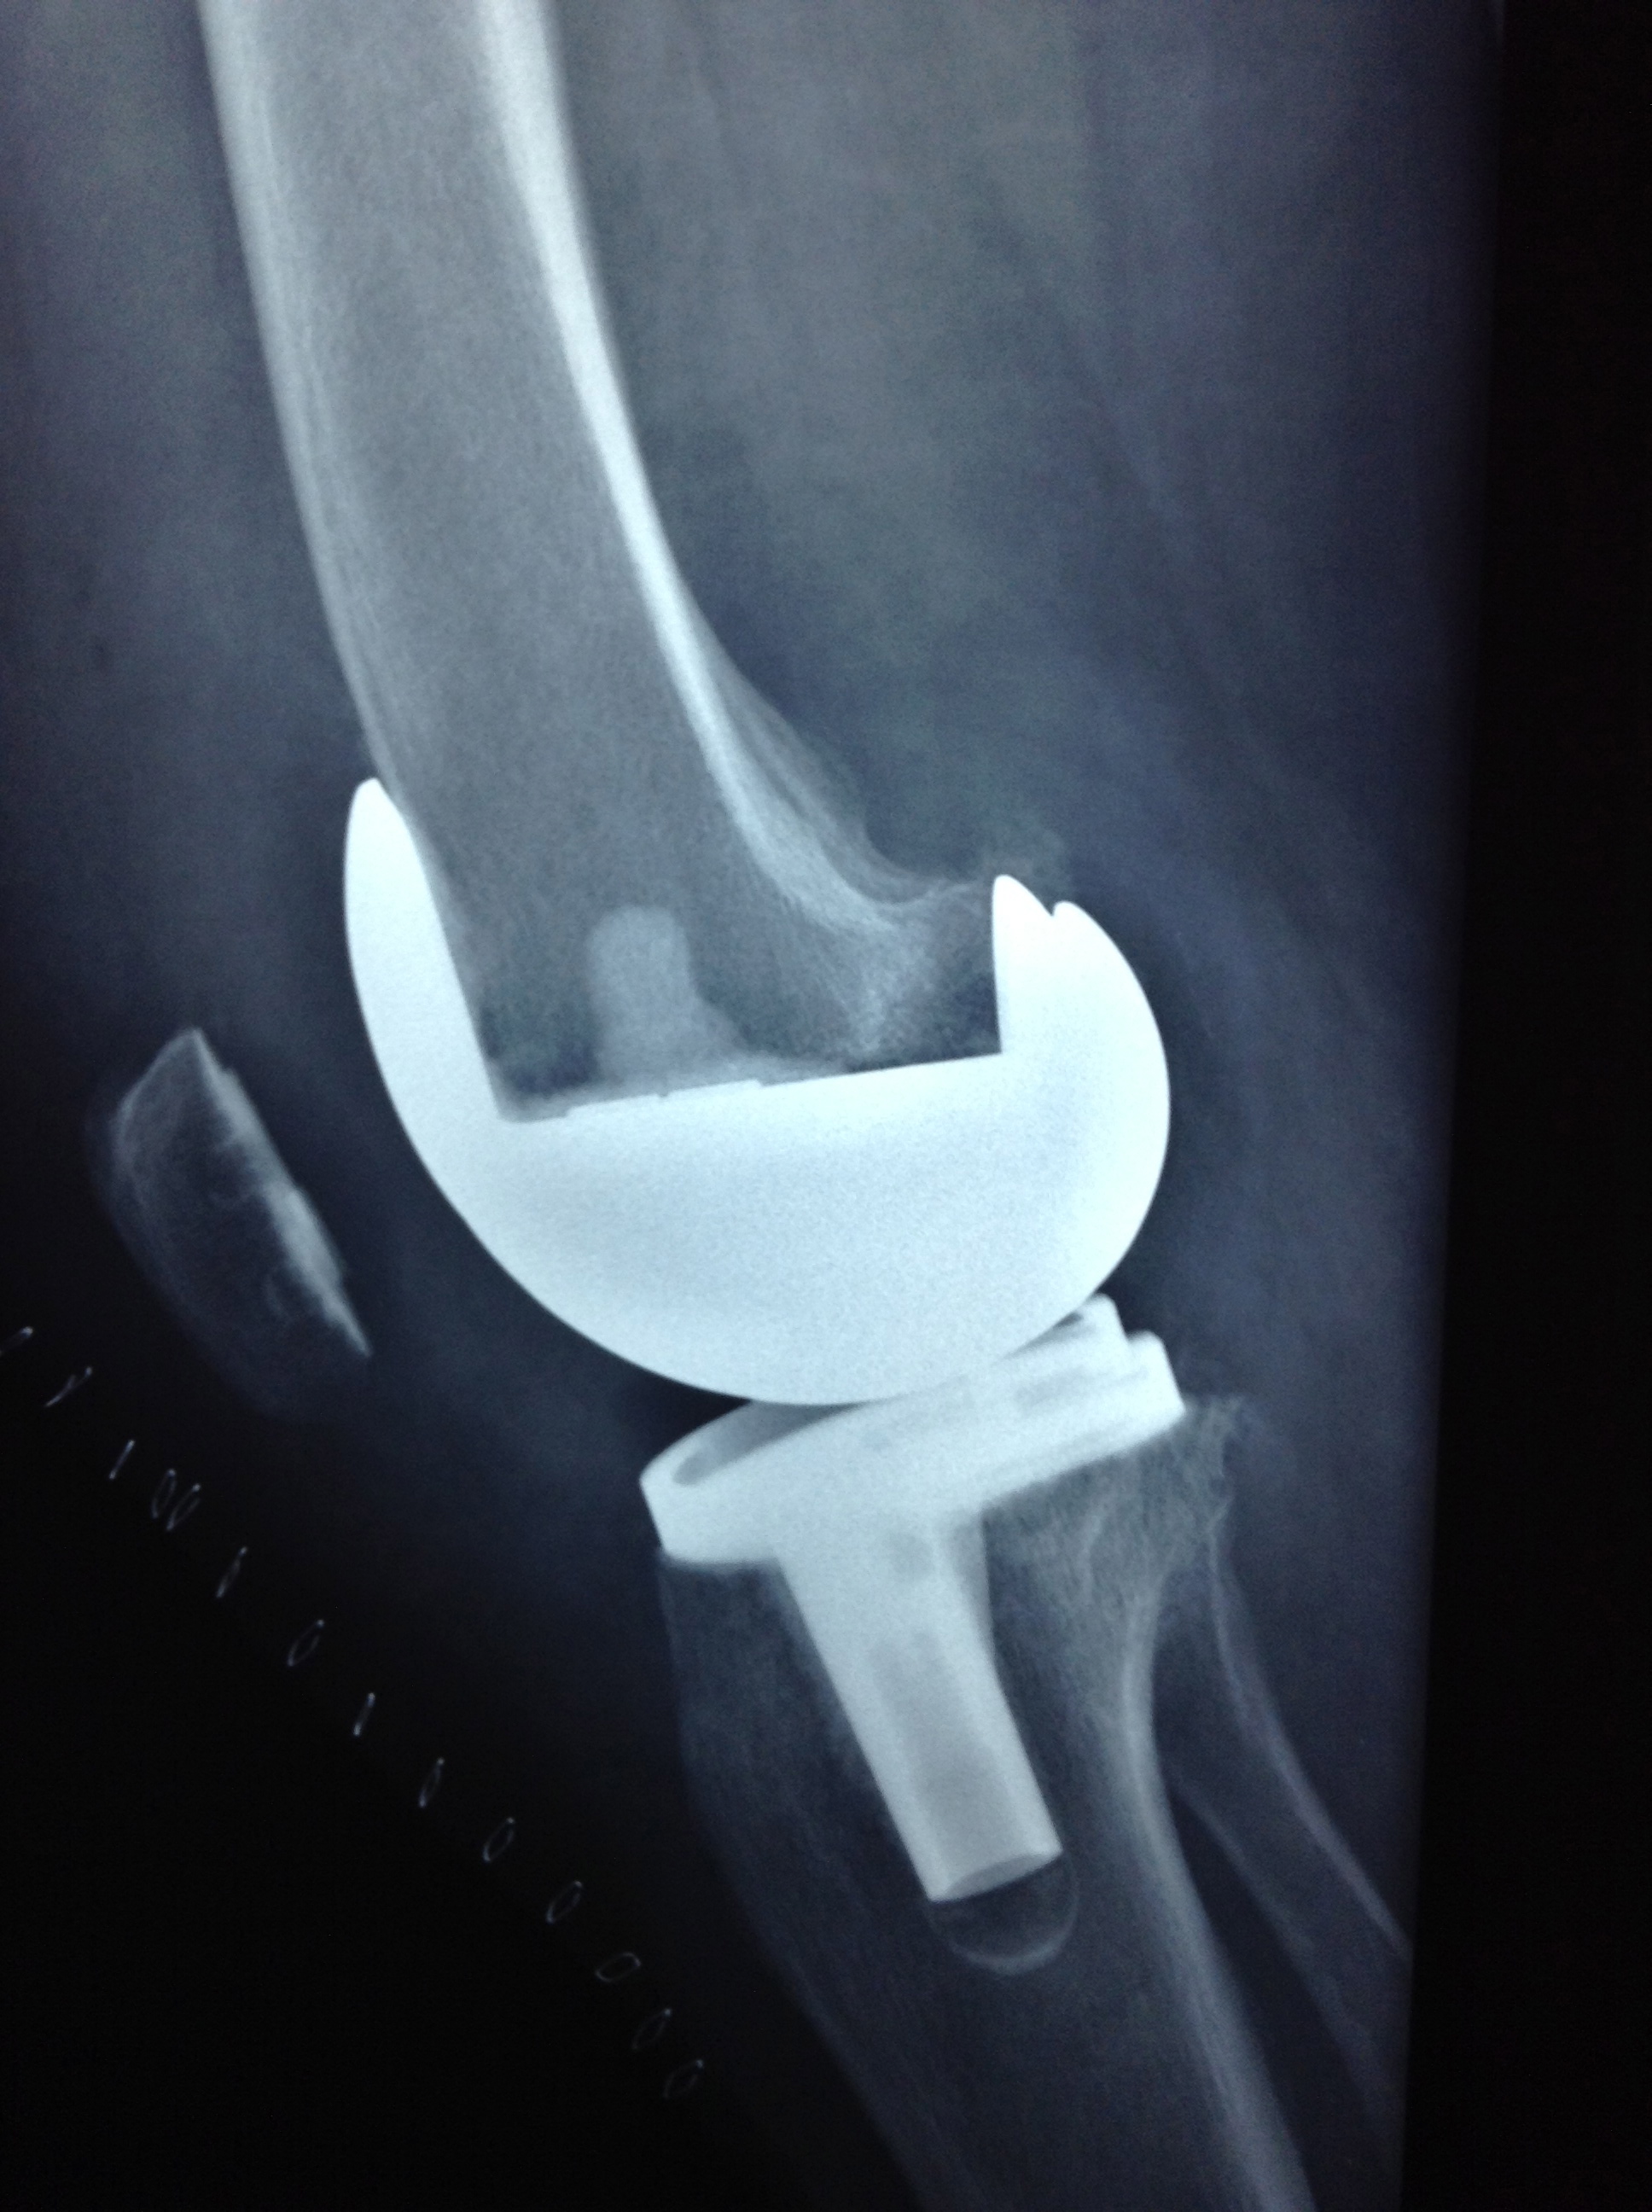

Revision Total Knee Replacement After Infection

• Revision Total Knee Replacement After Infection